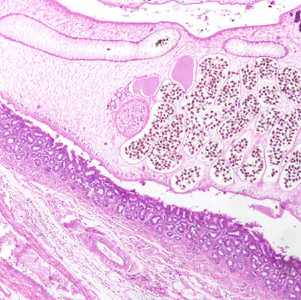

An immigrant from Korea presented with calculi in the intrahepatic biliary passages, cholangitis and early stage cholangiocarcinoma. Figures A–C show what was observed in a hematoxylin and eosin (H & E) stained liver tissue section. Figure A was captured at 40x magnification; Figures B and C at 200x magnification. The objects of interest in Figures B and C measured 30 micrometers on average. What is your diagnosis? Based on what criteria?

Figure A